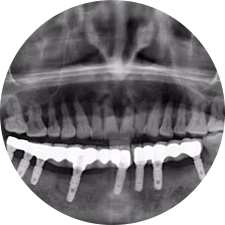

口腔種植是將人工牙根通過手術植入牙骨內,獲得牙槽骨牢固的支持,通過特殊的裝置和方式連接牙修復體,獲得與天然牙功能、結構以及美觀相似的效果。

術前患者CBCT口掃1:1三維重建,模擬手術過程及預測術后治療效果,確定每顆植體植入的適合的種植位點、深度及角度,有效避免損傷頜骨重要解剖結構,提高手術準確度與安全性。

惟德口腔種植體系是以患者感受為中心,取代傳統(tǒng)種植牙手術需要翻瓣、打孔、縫合,術前、術中、術后的繁復流程,采用3D導航微創(chuàng)準確種植技術,通過數(shù)字化CAD/CAM掃描技術獲得缺牙患者口腔數(shù)據(jù),以數(shù)據(jù)為基礎重建口腔模型進行模擬種植。

術前將患者口內的CBCT數(shù)據(jù)及咬合關系上傳到計算機中,建立1:1三維重建,模擬手術過程及預測術后治療效果,找出較佳種植位點、深度及角度,獲取實際種植體在頜骨內的具體三維位置,有效避免損傷頜骨重要解剖結構,大大降低手術風險,提升種植成功率。